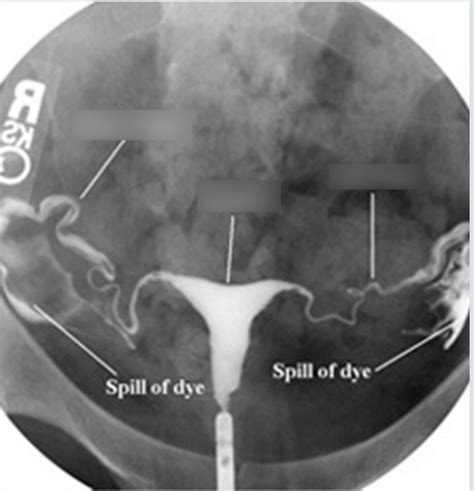

So, guys, what is an HSG X-ray ? At its core, an HSG X-ray, or hysterosalpingogram, is a special kind of imaging test that doctors use to get a good look at your uterus and fallopian tubes. Think of it as a sophisticated way to check if everything’s in the right place and functioning as it should in your reproductive system. The ‘HSG’ part stands for Hystero (uterus), Salpingo (fallopian tubes), and Gram (writing or recording), so it literally means a ‘writing of the uterus and tubes.’ This test is particularly crucial when a couple is experiencing difficulty getting pregnant, as it can help pinpoint specific issues that might be hindering conception. The procedure involves using a type of contrast dye and X-rays to create detailed images. The dye is introduced into the uterus through the cervix, and as it fills the uterine cavity and travels through the fallopian tubes, the X-rays capture its path. This allows your doctor to see the shape and size of your uterus, check if the fallopian tubes are open (patent), and identify any blockages, abnormalities, or scar tissue that could be causing problems. It’s a really valuable diagnostic tool because it gives a direct visual of these internal structures, which other tests might not be able to provide as clearly. We’ll get into the nitty-gritty of how it’s performed and why it’s such a big deal in just a moment, but for now, just remember it’s all about visualizing your uterus and fallopian tubes to understand reproductive health better.

Alright, let’s talk about the actual procedure, guys. Knowing what to expect can really ease any anxiety you might have about undergoing an HSG X-ray . First off, it’s important to know that the best time to schedule your HSG is usually shortly after your period ends but before ovulation occurs . This is because you definitely don’t want to be pregnant when you have this test done, and this timing ensures that. You’ll likely be asked to take some over-the-counter pain relief, like ibuprofen, about an hour before the procedure to help minimize any cramping. When you arrive at the clinic or hospital, you’ll change into a gown. The procedure itself is typically done by a radiologist or a gynecologist, often in a radiology suite. You’ll lie on an examination table, similar to how you would for a Pap smear. The doctor will then insert a speculum into your vagina to visualize the cervix, just like during a Pap test. Next, a thin catheter is gently inserted through the cervix into the uterus. This might feel a bit uncomfortable or cause some mild cramping. Once the catheter is in place, the contrast dye will be slowly injected through it. As the dye fills your uterus and flows into the fallopian tubes, the radiologist will take a series of X-ray images. You might feel some pressure or more cramping as the dye is injected. Some women describe it as feeling like menstrual cramps, while others find it more intense. It’s usually over fairly quickly, typically taking about 15-30 minutes from start to finish. After the X-rays are taken, the catheter is removed. You’ll then be able to get up and go about your day, though you might experience some mild cramping or spotting afterward. It’s really not as bad as it sounds, and the information it provides is invaluable!